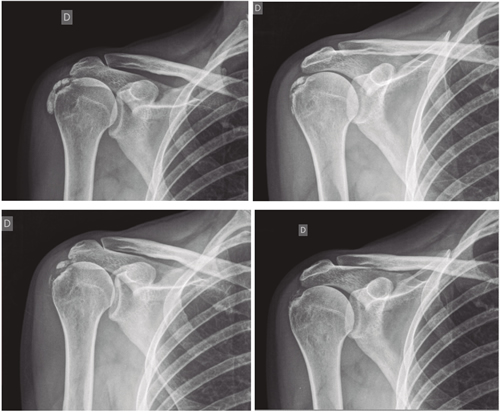

El número promedio de sesiones en nuestra serie fue de 20. El criterio para continuar o suspender el tratamiento fue la evolución radiológica y clínica (Figuras 4 y 5). Las intervenciones se realizaron hasta un máximo de 40 sesiones. Perrón trató a sus pacientes por 9 sesiones (3 sesiones semanales por 3 semanas) (14). Leduc trató con 10 sesiones (3 por semana las dos primeras semanas; y luego una semanal por 4 semanas) (15). Rioja-Toro trató a sus pacientes por 40 sesiones (5 veces por semana) y los evaluó a las 20 y a las 40 sesiones (3). Chico-Álvarez trató a sus pacientes entre 15 y 30 sesiones dependiendo de la evolución radiológica (5 veces por semana) (1).

Fig. 4. Paciente mujer de 47 años con tendinitis calcificante de supraespinoso derecho, de tipo formativa, quien tras 30 sesiones de iontoforesis disminuyó el dolor medido por EVA de 6/10 a 3/10 y la calcificación de 38 mm a 8 mm (valoraciones al inicio, a las 10, a las 20 y a las 30 sesiones, respectivamente).